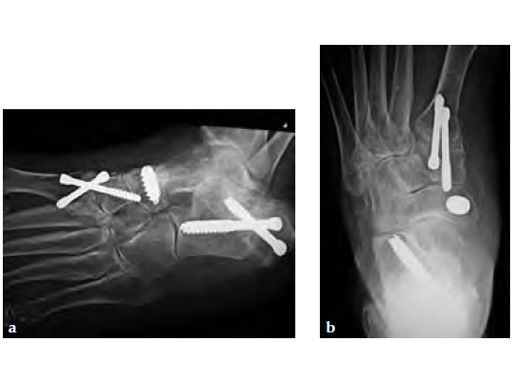

Stage II of her left posterior tendon dysfunction and tarso/metatarsal, instability visible on x-ray (see Fig 1a-c).

A medializing calcaneal osteotomy was performed and fixed with two 6.5 mm HCS, a flexor hallucis longus transfer to her navicular is secured with an interference 7 mm screw and a lapidus procedure fixed with two crossing 4.5 HCS (see Fig 2a-b).